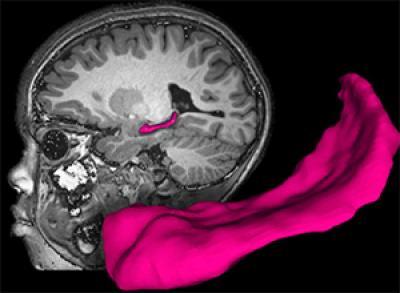

Using magnetic resonance imaging (MRI), the researchers found that poor children with parents who were not very nurturing were likely to have less gray and white matter in the brain. Gray matter is closely linked to intelligence, while white matter often is linked to the brain's ability to transmit signals between various cells and structures.

The MRI scans also revealed that two key brain structures were smaller in children who were living in poverty: the amygdala, a key structure in emotional health, and the hippocampus, an area of the brain that is critical to learning and memory.

An MRI scan highlights the hippocampus (pink) in a child's brain. Washington University researchers found that poor children with parents who were not very nurturing were likely to have a smaller hippocampus than those raised by more attentive parents.

(Photo Credit: Washington University Early Emotional Development Program)

Although the investigators found that poverty had a powerful impact on gray matter, white matter, hippocampal and amygdala volumes, they found that the main driver of changes among poor children in the volume of the hippocampus was not lack of money but the extent to which poor parents nurture their children. The hippocampus is a key brain region of interest in studying the risk for impairments.